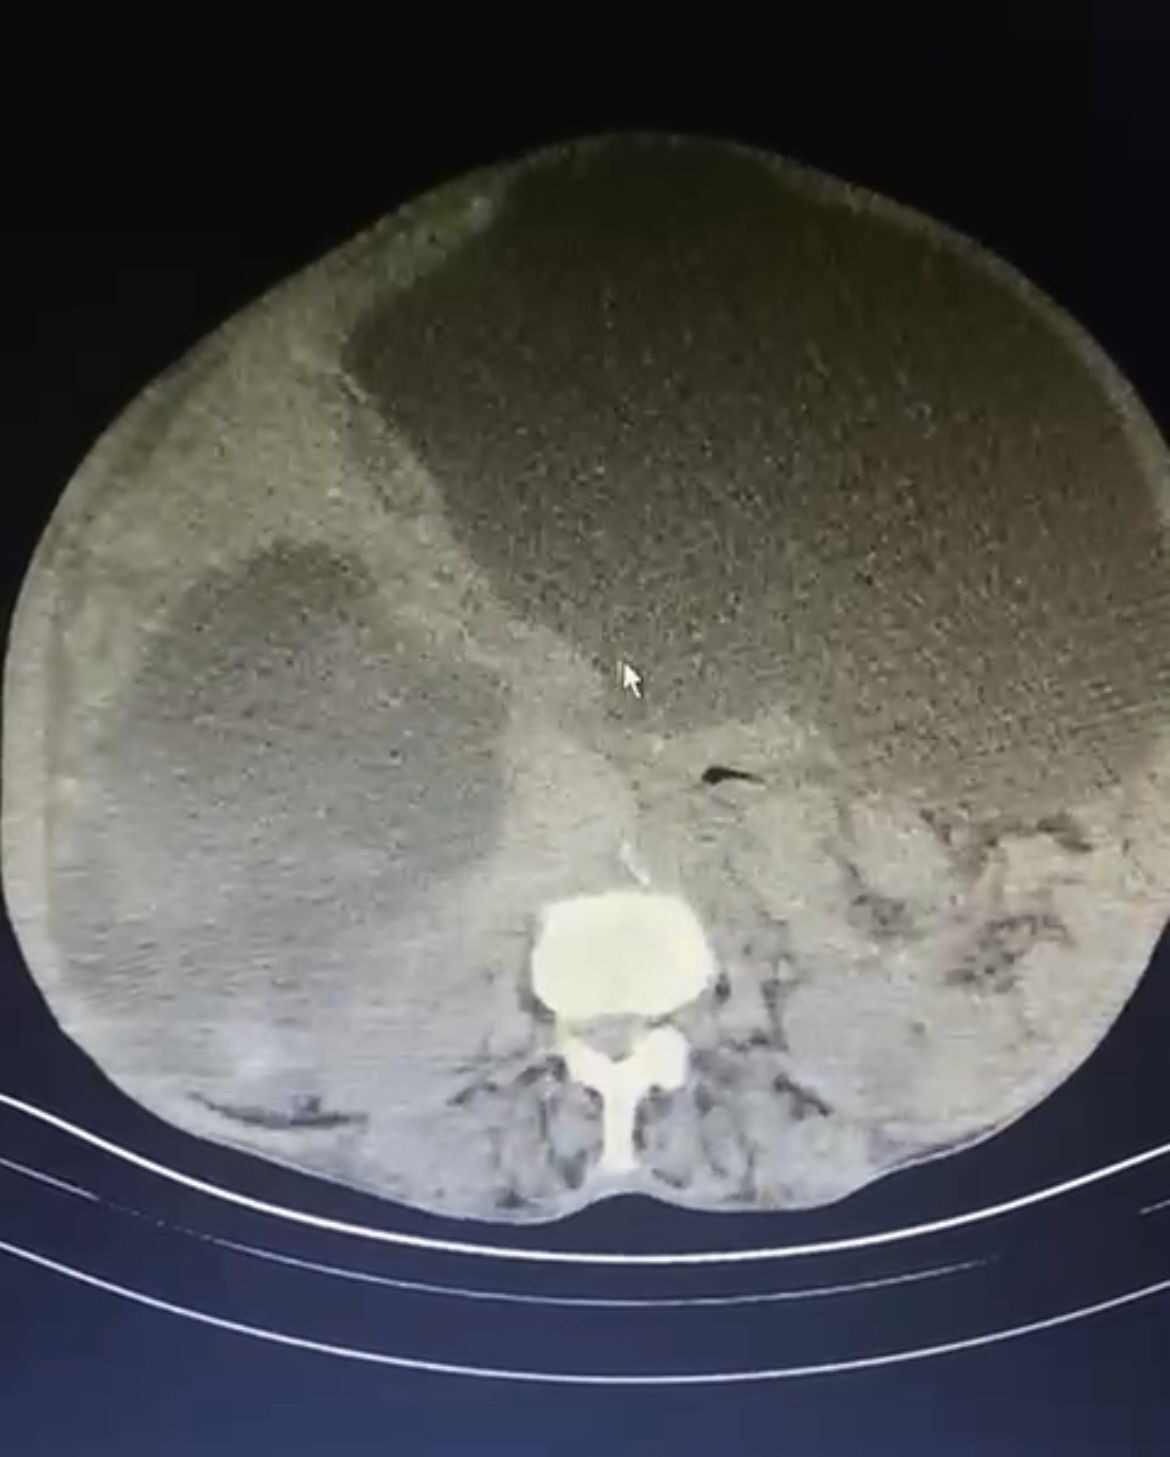

Kistlerin büyüklüğü dikkat çekerken Genel Cerrahi Uzmanı Opr. Dr. İsmet Çelik, dünya literatüründe tüm karnı dolduran ve 90 santime ulaşan kist görmediklerini belirterek Taşdelen’e yapılan gerekli tetkikler ve görüntüleme sonucu karaciğerinde üç adet kedi-köpek kisti (hidatik kist) tespit ettiklerini ifade etti. Çelik, başarılı geçen ameliyatın ardından hastanın sağlık durumunun iyi olduğunu ve sürecin yakından takip edildiğini belirtti.

Dünya literatüründe tüm karnı dolduran ve 90 santime ulaşan kist görmediklerini ifade eden Çelik, “Asiye Hanım, maalesef ihmal edilmiş bir hastamız. Bu kist, kedi ve köpeklerin dışkısı ve yediği yiyeceklerle bulaşan bir hastalık. Bu kist, genellikle tesadüfen yakalanabilir. Karaciğere yerleşir. Bu hastamızda da durum öyle olmuş. Ameliyat olamayacağı söylenip eve yollanmış. Bizler detaylandırıp ameliyat kararı aldık. Hastamızın karaciğerinde 3 ayrı kist vardı. Tüm karnı kist ile kaplıydı. 2 tanesinin tamamına çıkardık. Diğerini ise kontrolle alarak içini boşalttık. Dünya literatüründe tüm karnı dolduran ve 90 santime ulaşan kist görmedik. Ameliyatımız 2 saat sürdü. Hastamızın safra yolları kontrol edildi. Hastamızın durumu gayet iyi. Solunum cihazından bağımsız olarak kendi başına solunum yapabiliyor. En korktuğumuz şey; alerjik bir durumun olması. 90 santim çapındaki kist vücuda yayıldığı zaman alerjik bir durumda hastanın ölümüne sebep olabilmesi. Göremediğimiz yayılımlar için tedbir alıyoruz” diye konuştu.

YAPILAN TETKİKLERİNDE HASTANIN KARACİĞERİNDE ÜÇ ADET KİST TESPİT EDİLDİ.